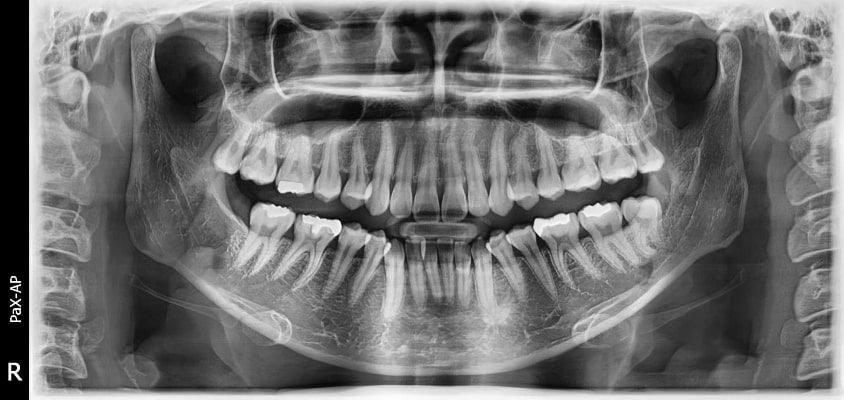

El innovador FOV proporciona un volumen en forma de arco que muestra una vista más amplia de la dentición en comparación con otros dispositivos del mismo FOV.

Normalmente, una imagen de 10x8.5 muestra el diente No.8. Sin embargo, cuando los terceros molares están tumbados sobre su lado hay una gran posibilidad de que el diente se corte de la imagen.

El “volumen en forma de arco” elimina esta posibilidad y muestra el área de dentición oculto.